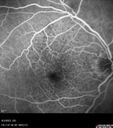

West Nile Virus Multifocal Choroiditis with later CNVM65 views77 year old female with vision loss in the left eye treated with Anti-VEGF